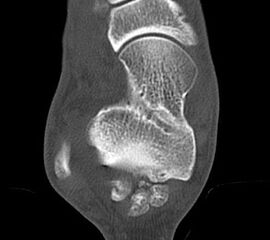

Abbildung Nr. 23 und 24, Video Nr. 4

Große osteophytäre Anbauten, welche die FHL-Sehne vollständig ummauern, sind ebenfalls sehr gut in der beschriebenen Technik adressierbar. Präoperatives CT und intraoperative Bildwandlerkontrolle im seitlichen Strahlengang (linke Seite).